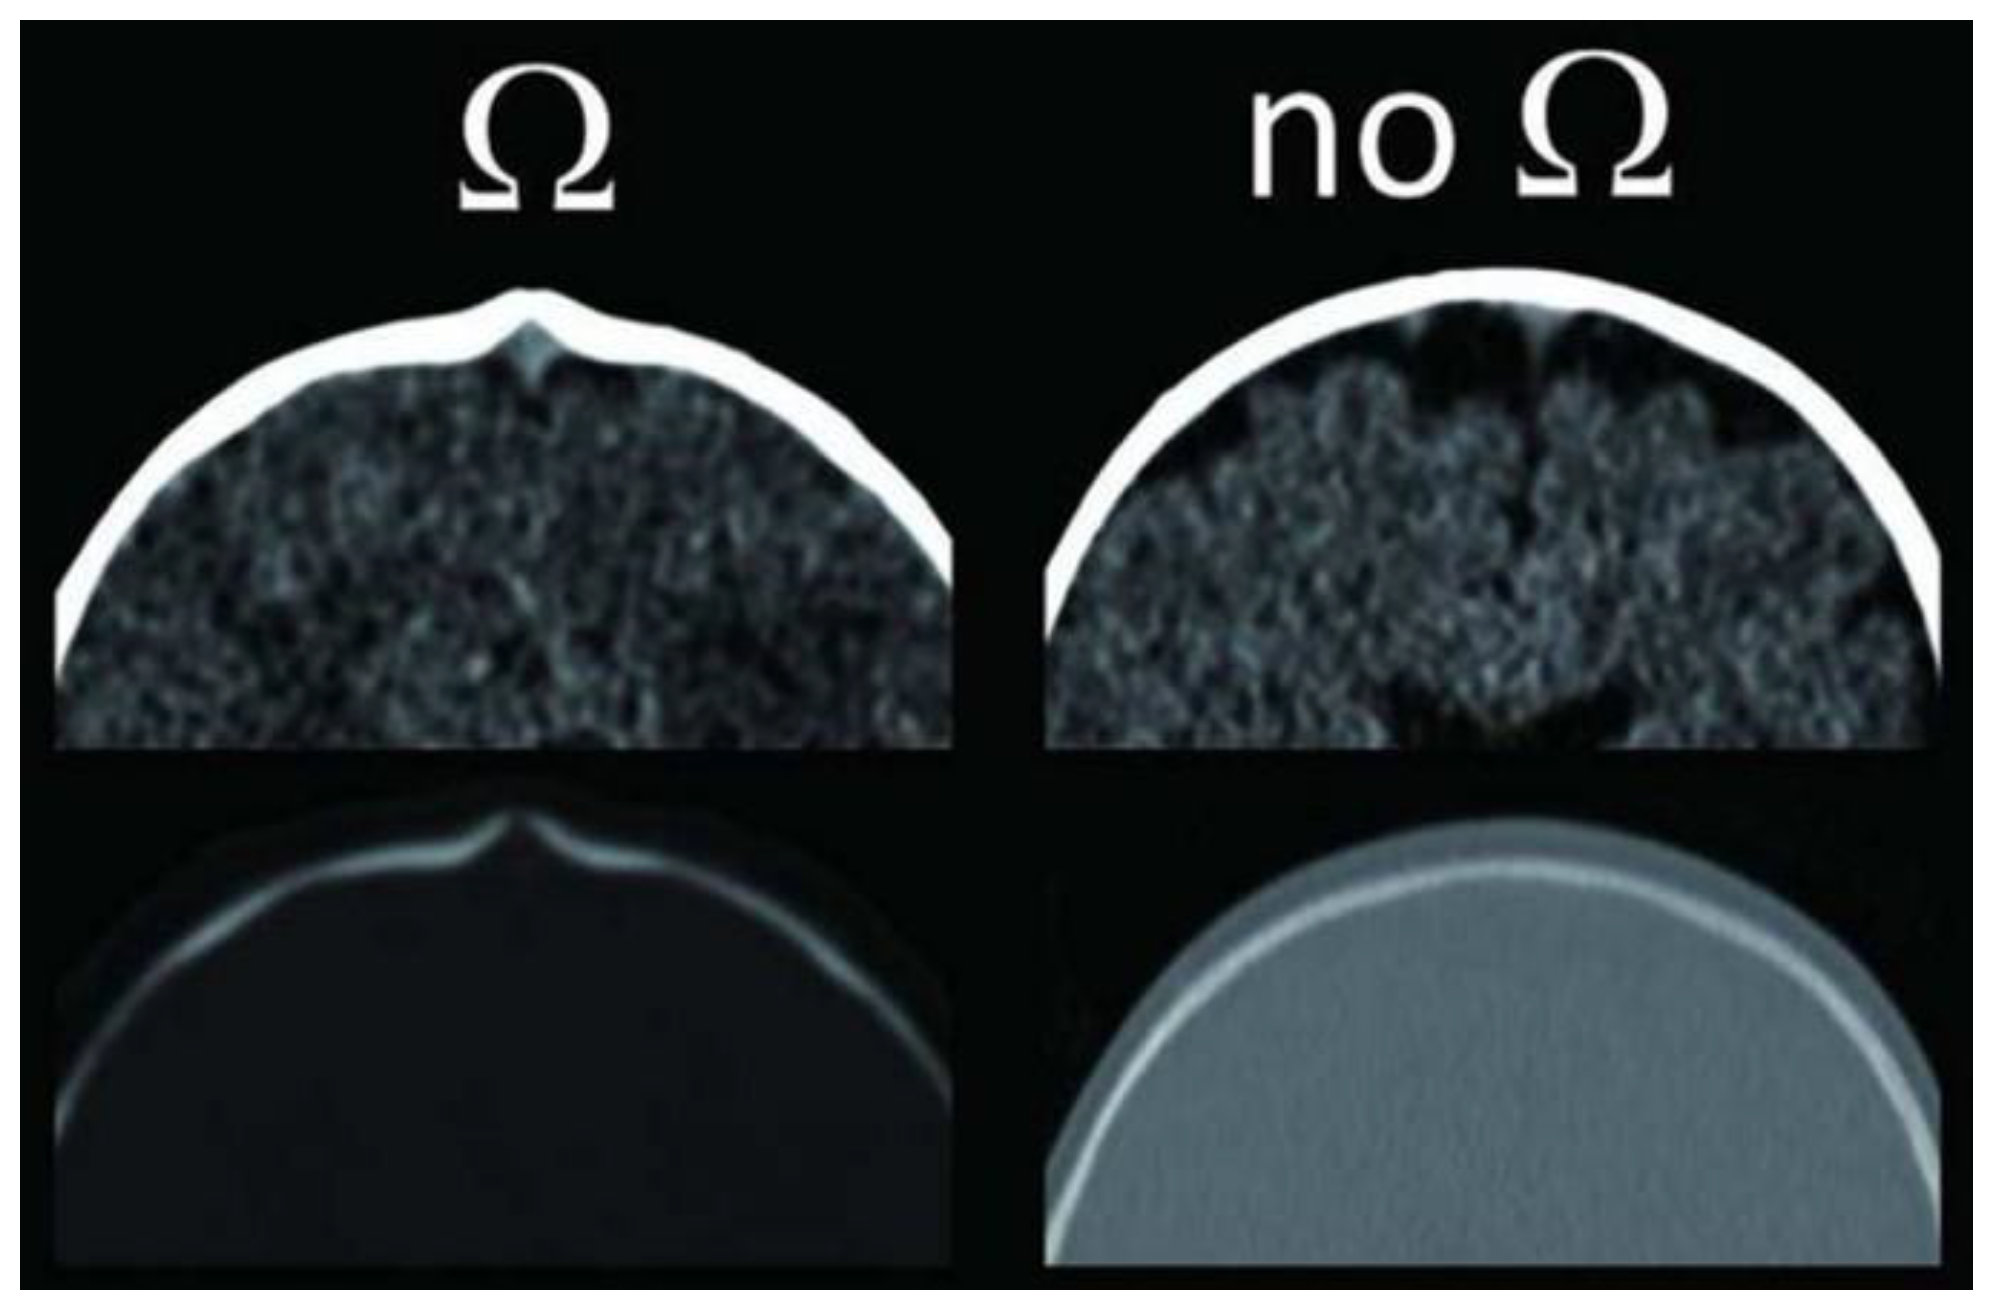

3. Radiology